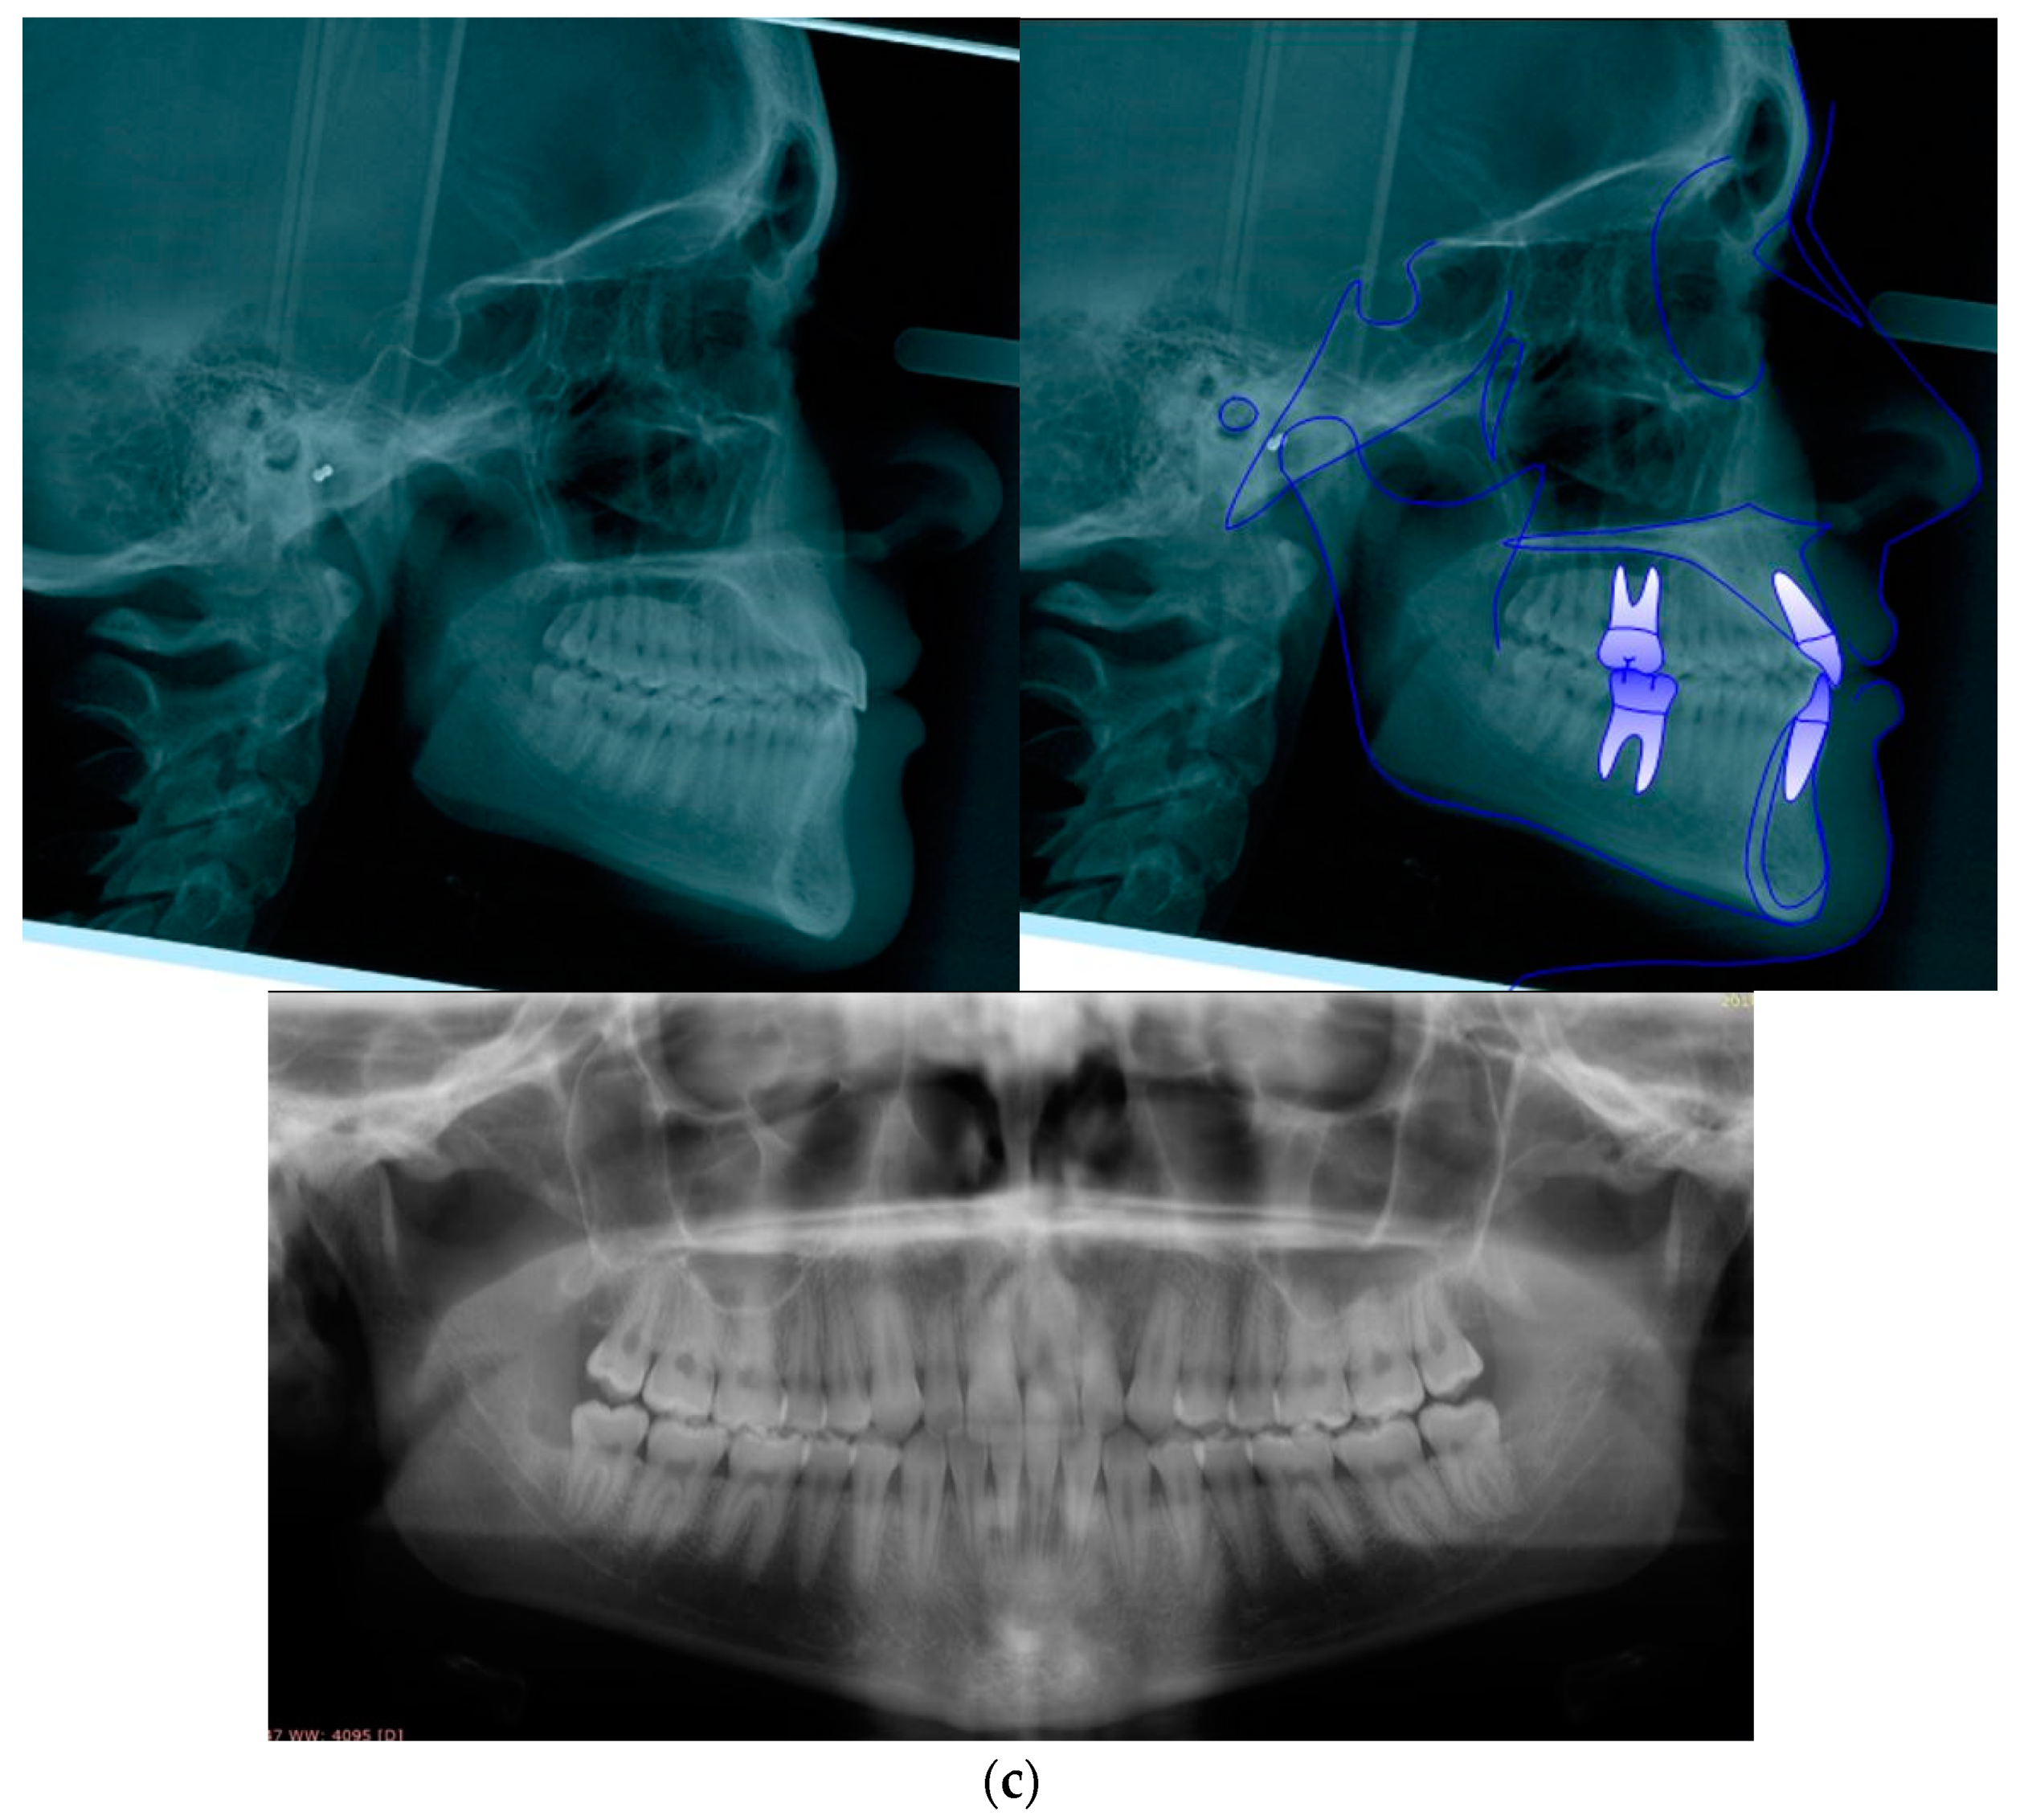

| Sagittal Jaw Relationship | ||

|---|---|---|

| Patient Value | Normal Value | |

| Maxillary position SNA (°) | 80.7 | 82 ± 3.5 |

| Mandibular position SNB (°) | 81.0 | 80 ± 2.5 |

| Sagittal jaw relation ANPg (°) | −0.3 | 2 ± 2.5 |

| Vertical jaw relationship | ||

| Maxillary inclination SN^ANS-PNS (°) | 8.3 | 8 ± 3 |

| Mandibular inclination SN^GoGn (°) | 30.1 | 33 ± 2.5 |

| Vertical jaw relation ANS/PNS^GoGn (°) | 21.8 | 25 ± 6 |

| Dento-basal relationship | ||

| Maxillary incisor inclination U1^ANS-PNS (°) | 114.2 | 110 ± 6 |

| Mandibular incisor inclination L1^GoGn (°) | 85.7 | 94 ± 7 |

| Mandibular incisor compensation (L1-Apo) (mm) | 2.1 | 2 ± 2 |

| Dental relationship | ||

| Overjet (mm) | 2.8 | 3.5 ± 2.5 |

| Overbite (mm) | 2.0 | 2.5 ± 2.5 |

| Interincisal angle (°) | 138.2 | 132 ± 6 |